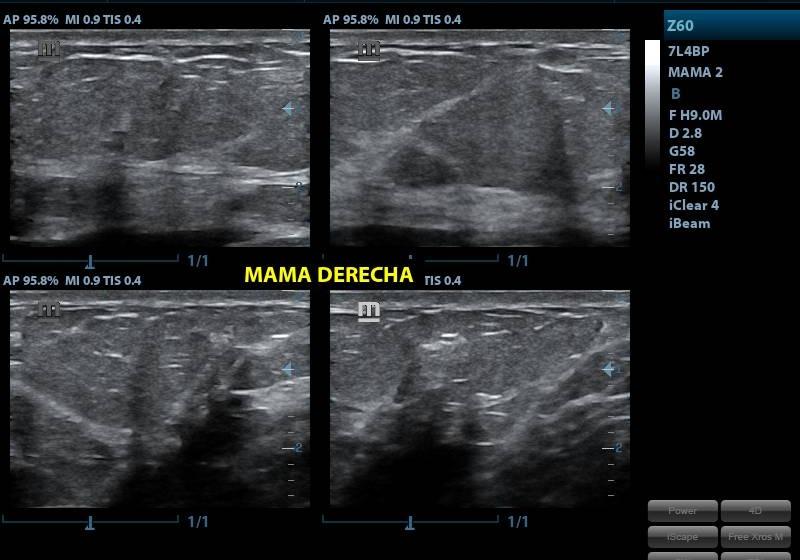

ECOGRAFIA DE MAMAS

CONDICIÓNNO REQUIERE PREPARACION PREVIA

TIEMPO20 MINUTOS

TIPO RESULTADOSIMAGENES ECOGRAFICAS

ESPECIFICACIONESes una prueba de imagen no invasiva que detecta lesiones o tumores que la mamografía no distingue. Se trata de una técnica que utiliza ultrasonidos y que en ningún caso sustituye a la mamografía de chequeo sino que presenta una alternativa a la radiación de la mamografía en mujeres jóvenes y en embarazadas.